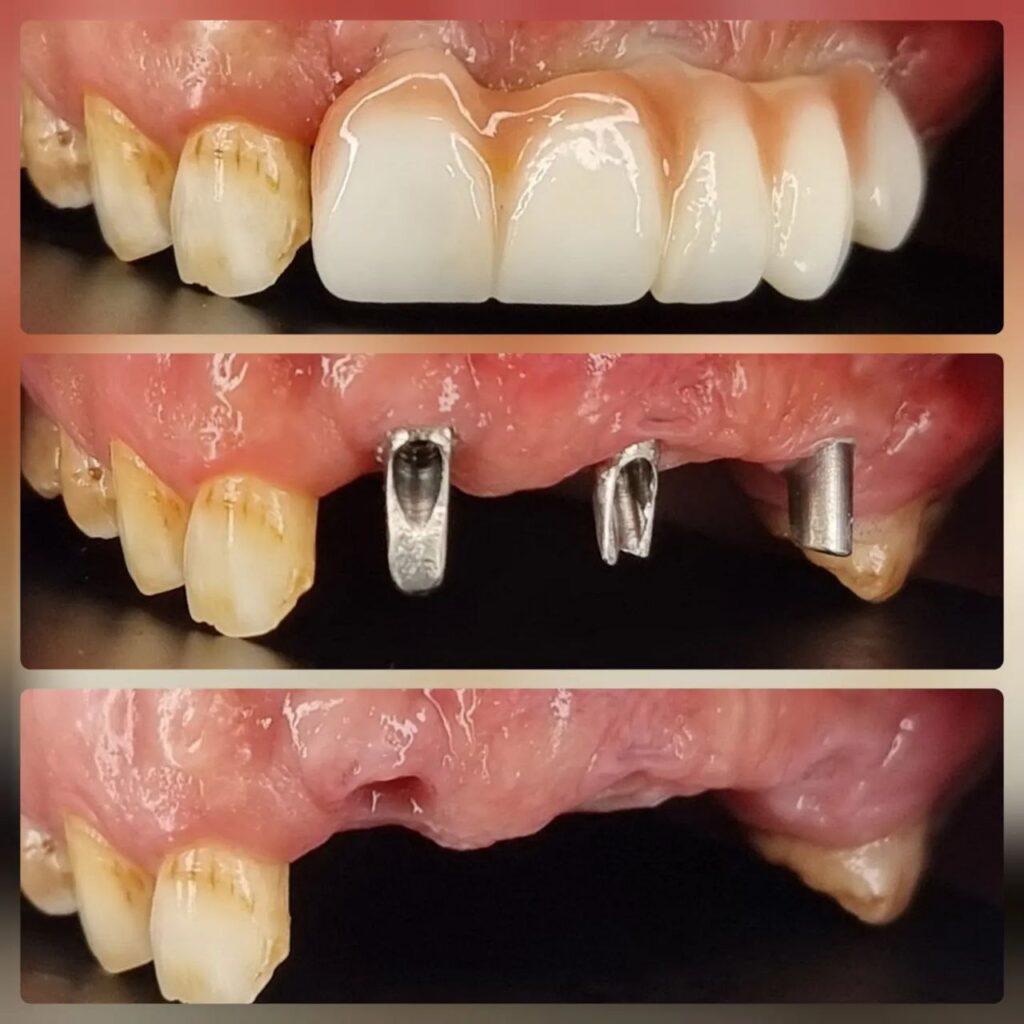

کاشت ایمپلنت دندان

اطمینان حاصل کردن از اینکه دندانهایتان به نحوی زیبا و طبیعی جایگزین شدهاند، از اهمیت بسیاری برخوردار است. ایمپلنت دندان به عنوان یک روش درمانی دائمی در دندانپزشکی شناخته میشود که حاصل آن، یک دندان زیبا و طبیعی در دهان شما خواهد بود.

هرچند که این روش درمانی هزینهی بیشتری نسبت به روشهای دیگر دارد، اما ارزش زیبایی که ایجاد میکند، قابل انکار نیست. ایمپلنتها به قدری شبیه به دندانهای طبیعی هستند که به سختی میتوان آنها را از دیگر دندانها تشخیص داد.